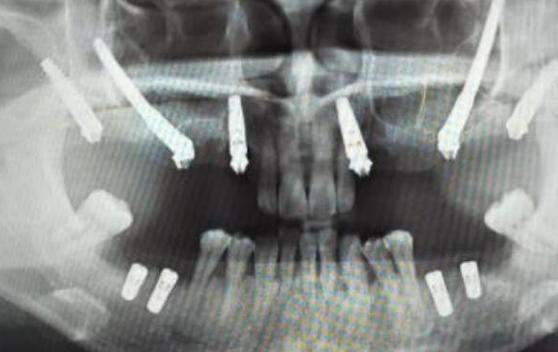

- 种植体穿入上颌窦: 种植体尖端可能穿透上颌窦底壁,进入窦腔,这会导致感染、疼痛、种植体松动、失败等严重后果。

针对骨量不足靠近上颌窦的情况,种植牙医生通常不会直接种植,而是会采用以下上颌窦提升术来增加骨量,确保种植体安全植入:

上颌窦提升术(也叫上颌窦底增高术)

这是解决上颌窦区域骨量不足的标准方法,其原理是通过外科手术,将上颌窦底壁的骨膜和黏膜(称为“上颌窦粘膜”)向上推起,在窦底和推起的粘膜之间创造一个空间,然后填入骨移植材料,诱导新骨形成,从而增加骨高度。